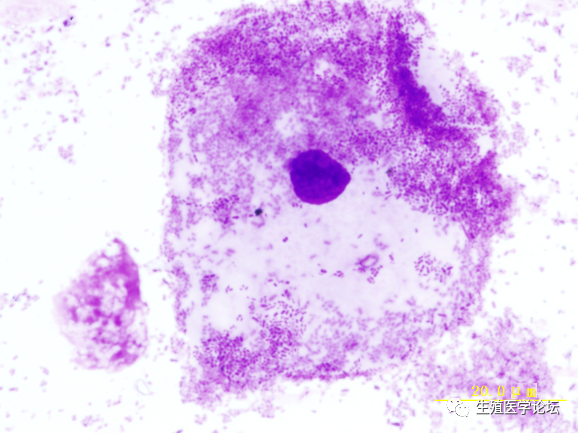

生精细胞在健康人精液中按数量、比例有序排出、常态脱落,如果生精细胞脱落的数量、比例及形态出现异常,将有可能引起精液质量改变,导致不育。生精细胞的异常脱落是睾丸生精功能障碍的直接反应和受损表现,而睾丸生精功能受损必然有一个过程,由于受损程度、受损时间及致受损的因素不同,其生精细胞发生病理性改变及脱落状况也不尽相同。

根据生精细胞脱落的数量异常、比例异常及形态异常,可作为衡量睾丸生殖功能的有效指标。生精细胞大量脱落,初级精母细胞阶段

发育阻滞,凋亡显著

如果生精细胞在某个阶段出现堆积、比例增高,可大致判断生精阻滞的阶段,其中初级精母细胞阶段最为常见,精子细胞阶段次之,精原细胞阶段少见。生精细胞不仅可以表现为数量和比例异常,还可以表现为形态异常,其形态特征主要以凋亡和胀亡为主,凋亡主要表现为细胞核固缩、边聚、突出、凋亡小体等,胀亡表现为细胞核膨胀、均质化、胞膜崩解等。细胞凋亡和胀亡代表两种不同的细胞死亡方式。根据生精细胞的异常脱落,对探索不育症的病因及发生机制有着重要价值,并可作为疗效观察和判断预后的重要指标。精子细胞阶段分化不良,多核、凋亡